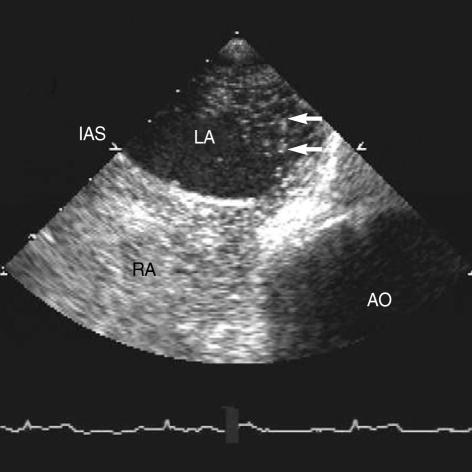

Air embolism is a rare complication of percutaneous nephrolithotomy. Patent foramen ovale, which is necessary in fetal circulation, is a potential route for emboli arising from the venous system to enter the systemic arterial circulation, resulting in paradoxical air embolism syndrome. A case of paradoxical air embolism during percutaneous nephrolithotomy is presented. To our knowledge, this is the first report of paradoxical air embolism associated with patent foramen ovale during percutaneous nephrolithotomy.

空气栓塞是经皮肾镜取石术的一种罕见并发症。卵圆孔未闭在胎儿循环中是必要的,它是静脉系统产生的栓子进入体循环动脉系统的潜在途径,可导致反常空气栓塞综合征。本文报告了一例经皮肾镜取石术期间发生的反常空气栓塞病例。据我们所知,这是经皮肾镜取石术期间与卵圆孔未闭相关的反常空气栓塞的首例报告。